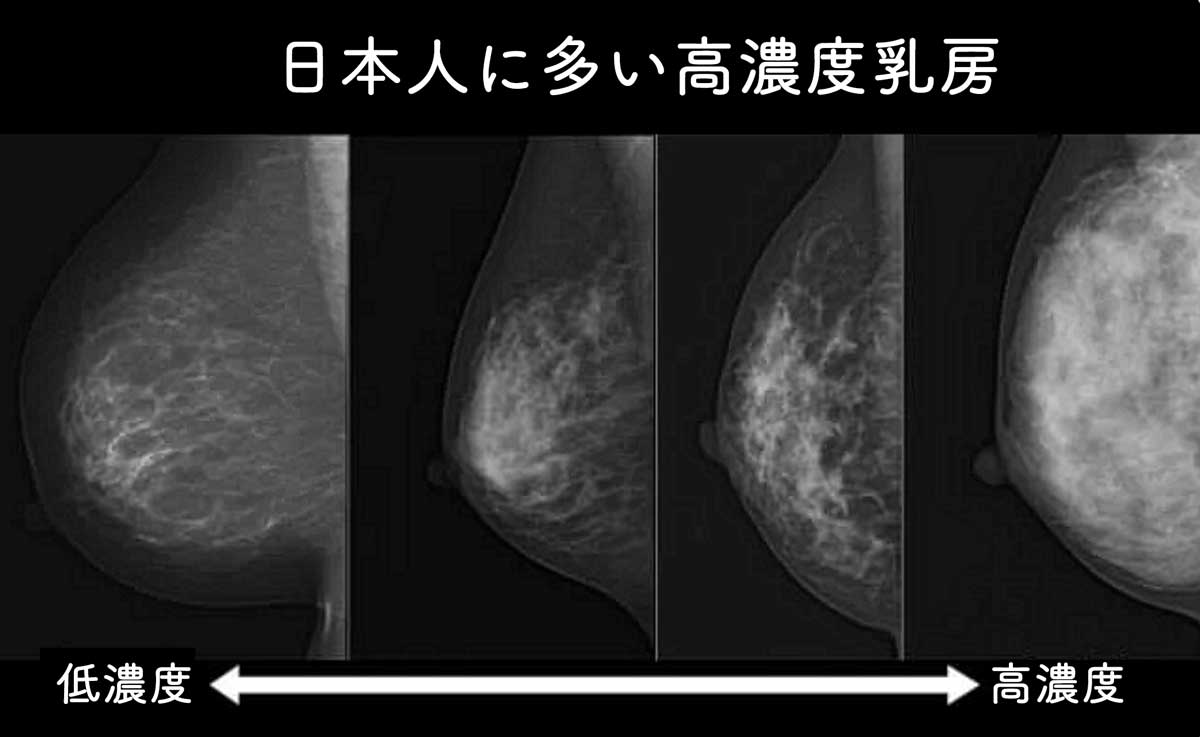

日本人に多い高濃度乳房

ドゥイブス・サーチでは、がんの組織が黒く映ります。

日本人女性に多い高濃度乳房(デンスブレスト)※1の方でも高い確率でがんを発見することが可能です。

※1…日本人の半数以上が乳腺が豊富にある高濃度乳房で、特に50歳以下に多いとされています。

70歳代ぐらいになると次第に乳腺が萎縮し、乳房のほとんどが脂肪になります。